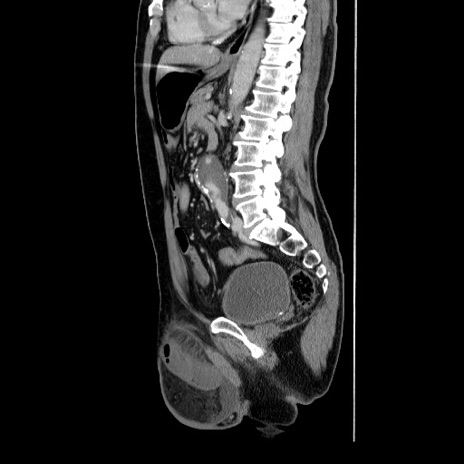

症例34(矢状断像)

症例